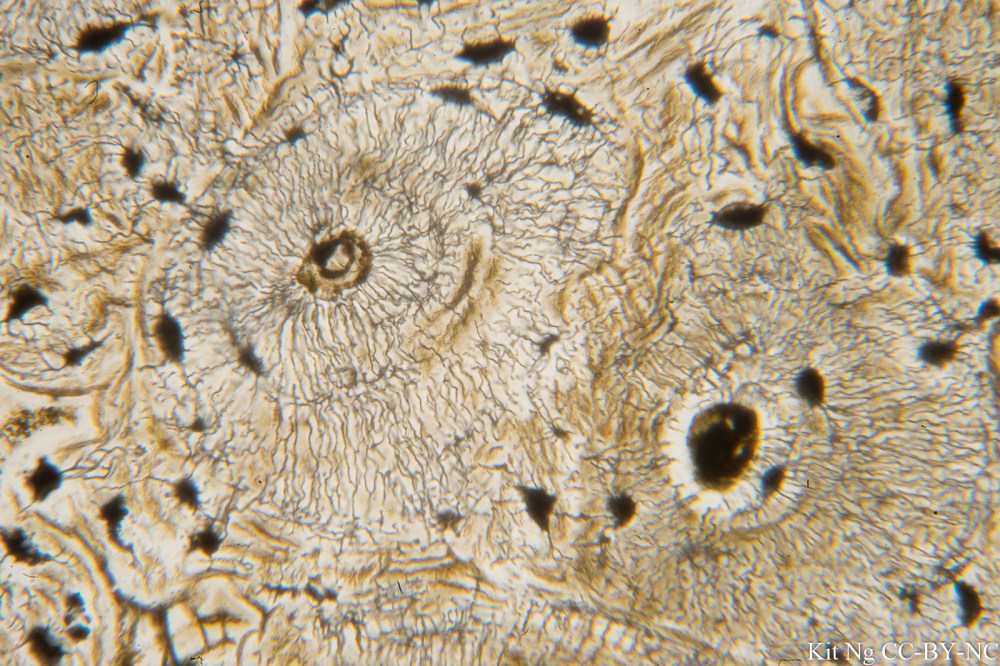

Compact bone.  (TM: 400x, picture taken with a Zeiss Planapo 40/1.0 Oil on Leica)

Compact bone.  A haversian system or Osteon could be seen on the left side.  (TM: 400x, picture taken with a Zeiss Planapo 40/1.0 Oil on Sony A7ii)